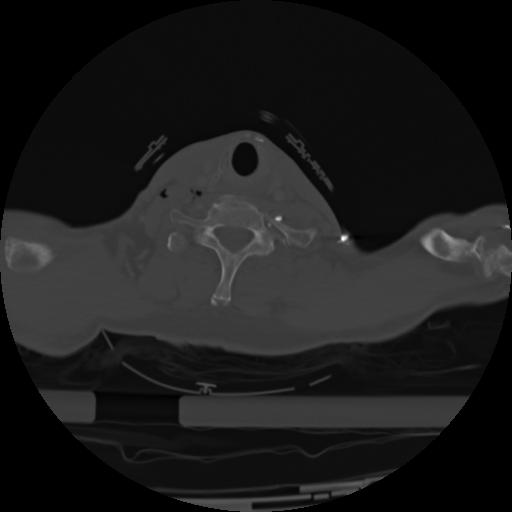

21 ANGIO,CE,Axial,3.0,ANGIO,,